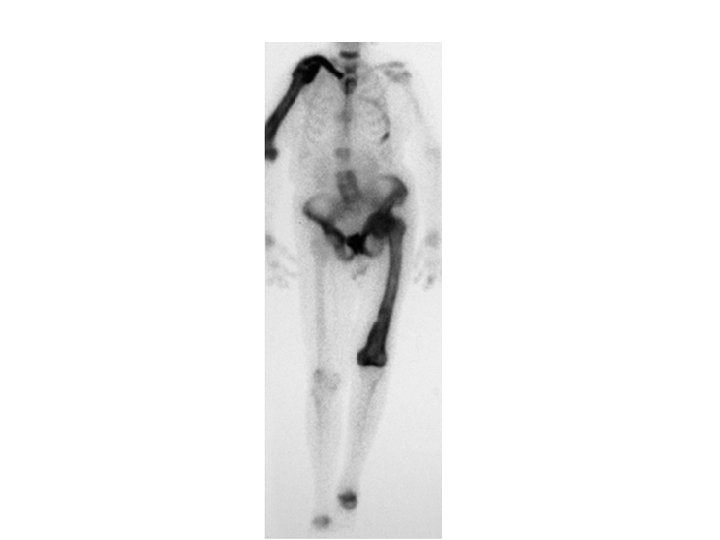

Bone Diseases Continued • Osteosarcoma – – – – Form of Bone cancer Typically in long bones of limbs and most often in 10 -25 age group Grows aggressively Painful eroding of bone Metastasizes (moves to) lungs Treatment: amputation of affected bone or limb, chemotherapy Survival rate of 50% (if caught early)

osteosarcoma